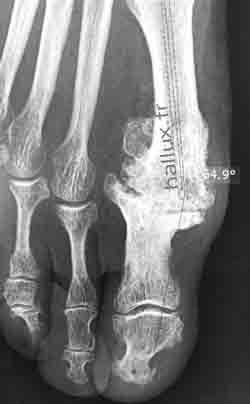

1 - L'ARTHRODESE :

Elle constitue l'intervention de référénce.

Elle supprime immédiatement la douleur (et la mobilité !) mais le réglage de la position est important en maintenant un espace avec le 2° orteil et une rotation neutre.

Elle est proposée sans restriction chez l'homme (90% sont satisfaits) mais certaines femmes refusent l'idée de ne plus porter de talons hauts.

Les contre-indications en sont l'arthrose talo-crurale ou interphalangienne du gros orteil.

Le but de l'intervention est de réséquer les ostéophytes, gênant le chaussage et bloquer la première articulation métatarso-phalangienne par avivement des surfaces articulaires et ostéosynthèse par agrafes, vis ou broches.

Des chaussures post-opératoires sont nécessaires 45 jours pour limiter le risque de pseudarthrodèse (défaut de consolidation).